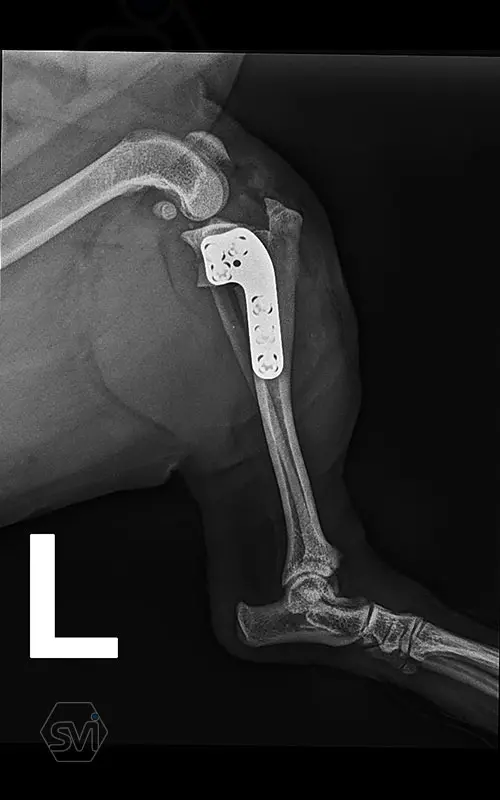

Multifunctional symmetrical long polyaxial locking plate - designed for the treatment of fractures close to joints

A special member of the polyaxial locking plate family is the multifunctional long plate, which is an extended version of the well-known symmetrical TPLO plate, with a 5-3 hole distribution. The plate also received a DCP hole to be able to create compression, and there is a mini-hole on the head end to facilitate the placement of the temporarily used K-nail. The burrs on the side facing the bone surface are intended to reduce the contact surface between the plate and the bone (limited contact).

The plate is a member of the large polyaxial locking family, suitable for 2.7-3.5-4.0 mm screws. We recommend it for fixaton of fractures close to joints, wedge osteotomies with axis correction (closing and opening), or for CWTO operations.